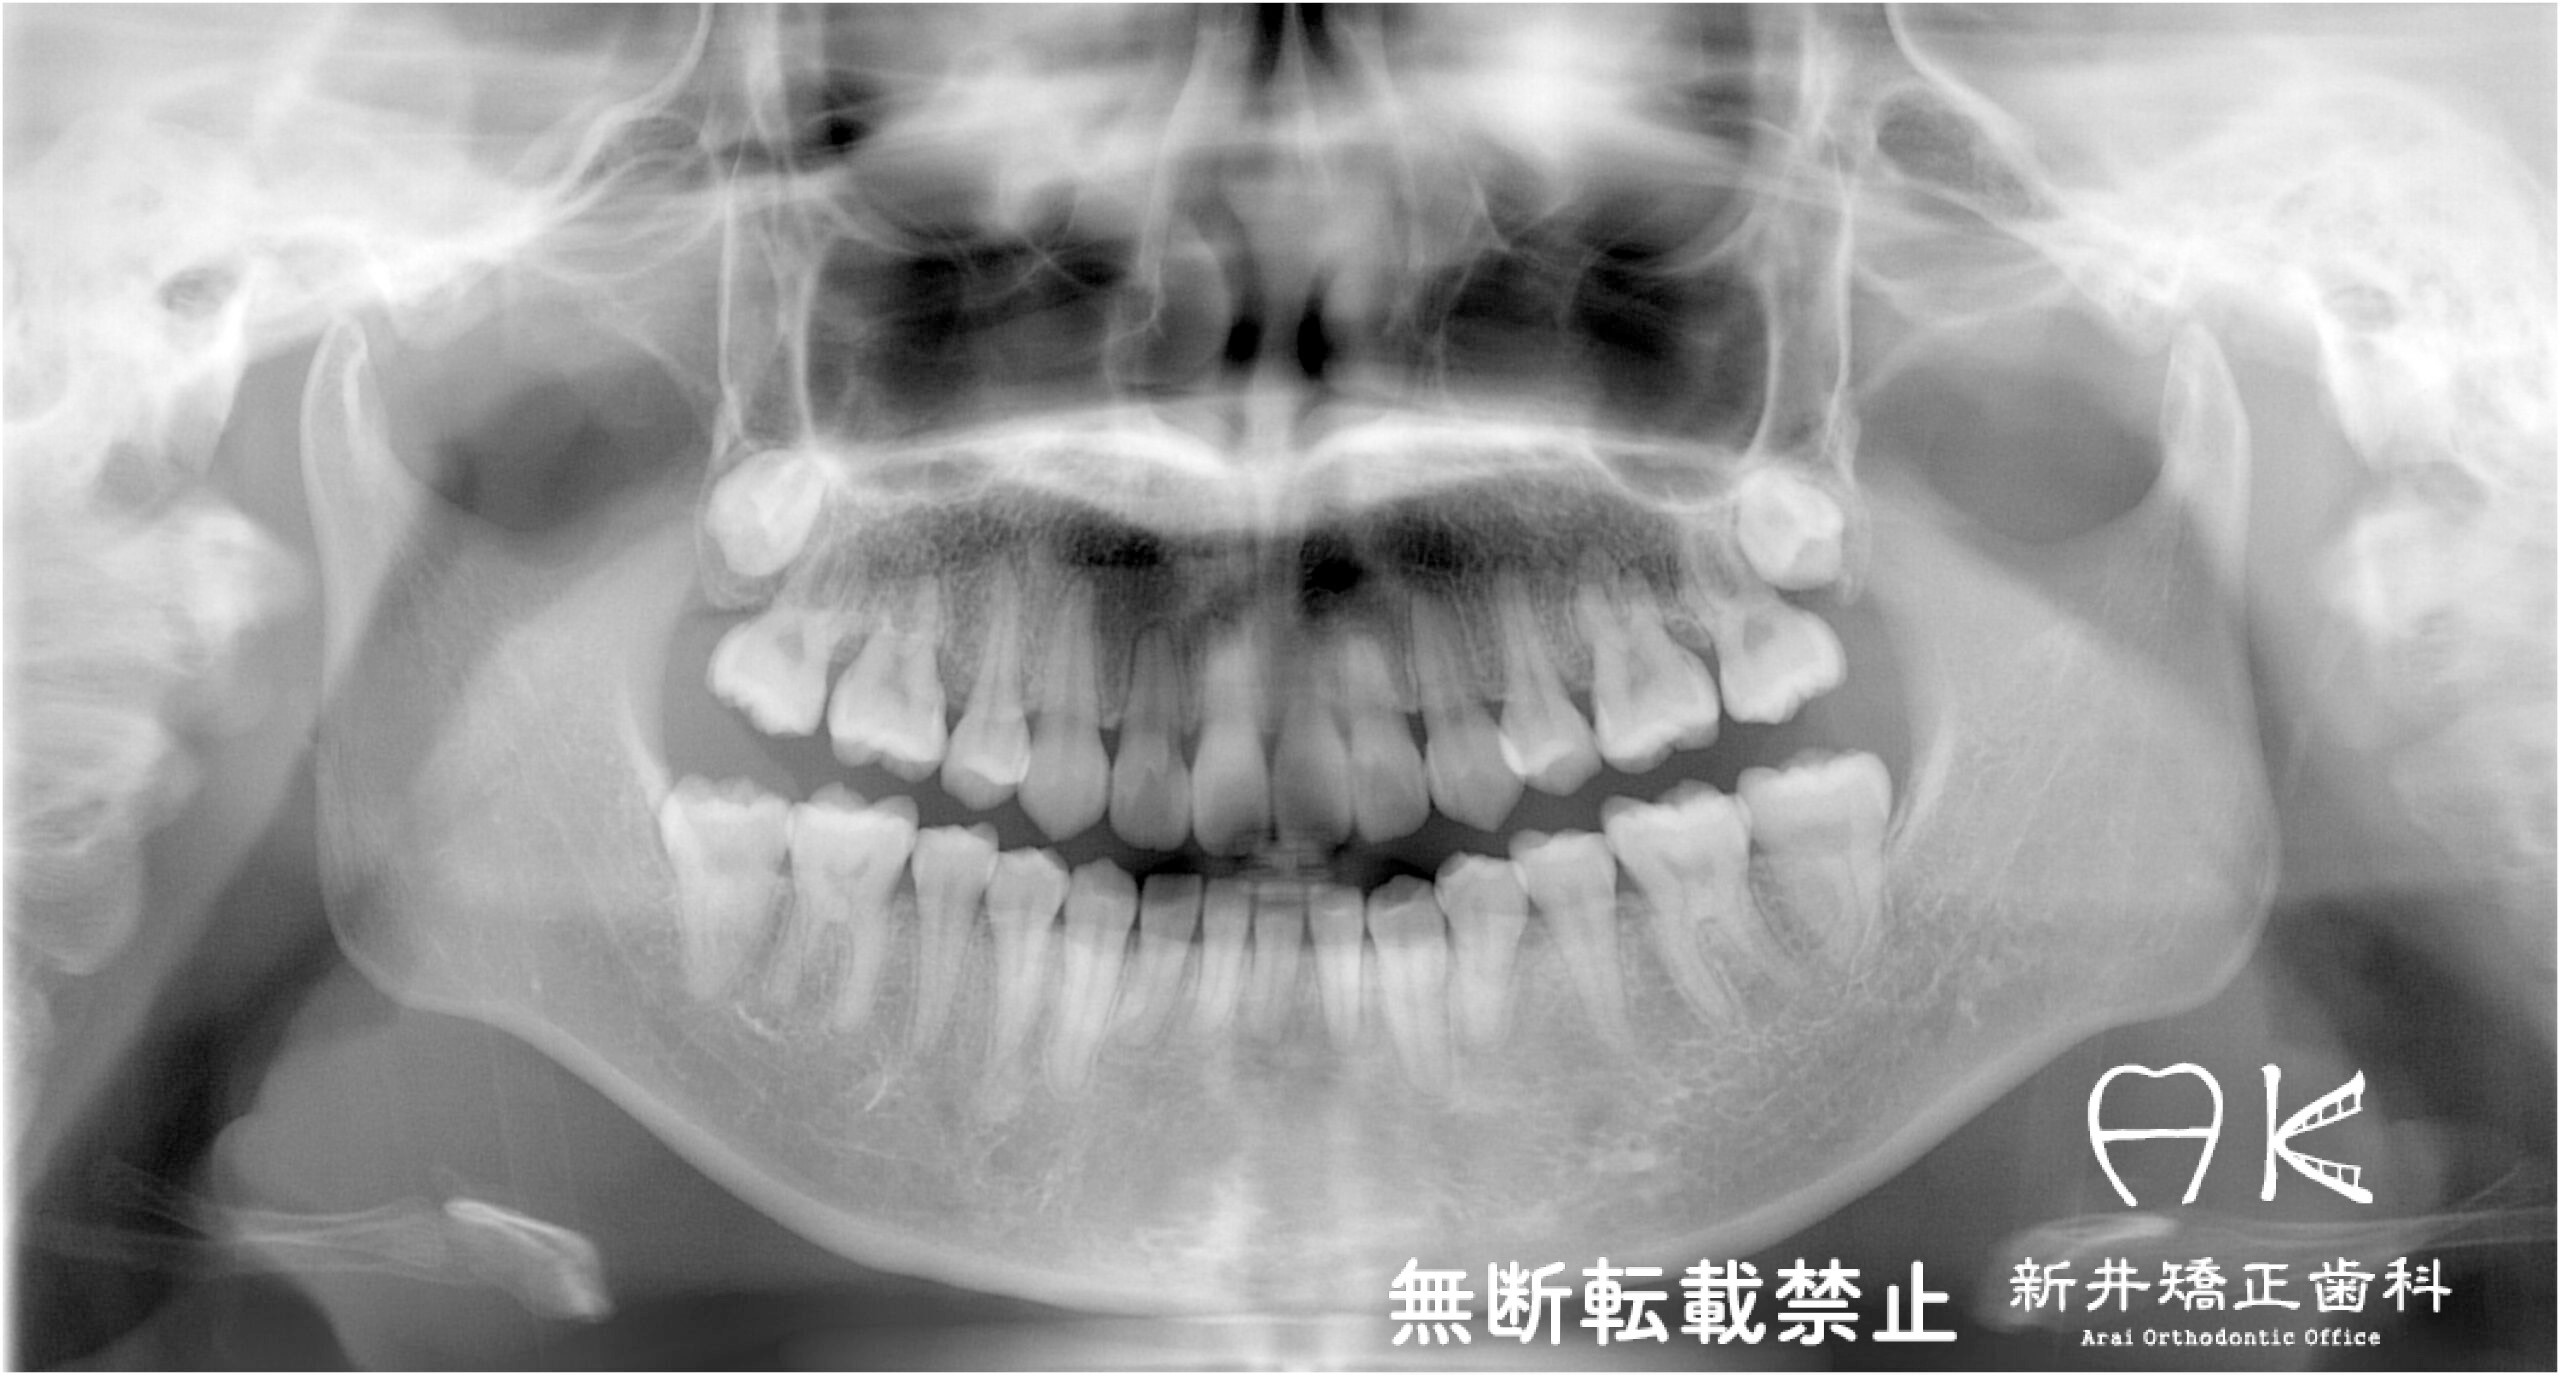

治療中

![]() | ||

![]() | ![]() | ![]() |

![]() |